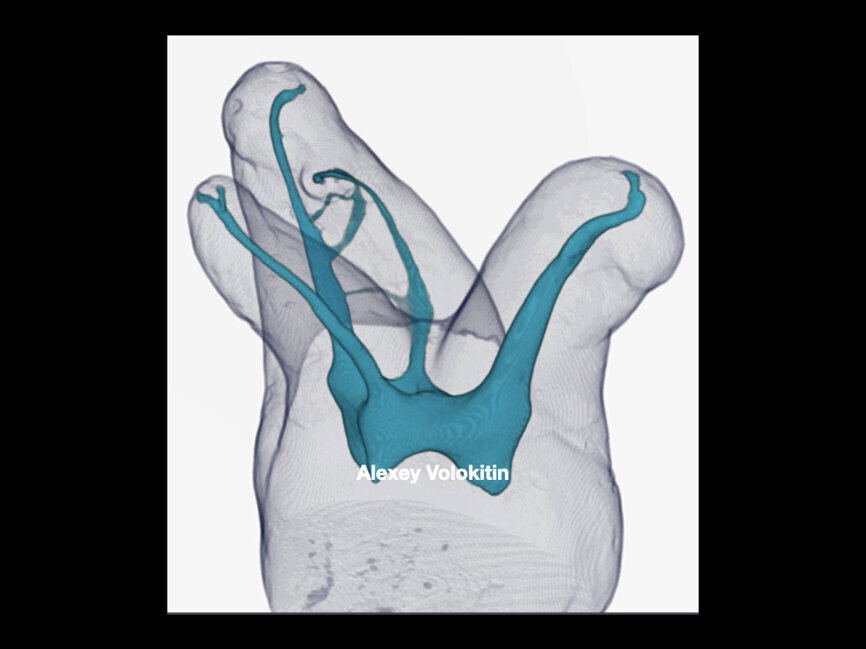

For shaping, you need to start, after establishing a glide path, with 21 mm stainless-steel hand files. I use a 17 mm orifice opener because it allows me to work way in the back with indirect vision, and this step will shape the first part of the canal, making it easy for the remaining rotary files to follow the path that has been created. The final radiographs revealed four separate root canals (Fig. 3). Figure 4, a micro-CT scan done by Dr Volokitin, shows almost the same anatomy.

Figure 7 shows an immediate postoperative radiograph of the treatment. A micro-CT scan of a similar root canal system is shown in Figure 8.

The immediate postoperative radiograph in Figure 10 does not show it, but an image at a further 15° angle would clearly show the independent exit of the second mesiobuccal canal. A micro-CT scan of a similar anatomy—as we can never find two identical anatomies—is illustrated in Figure 11.